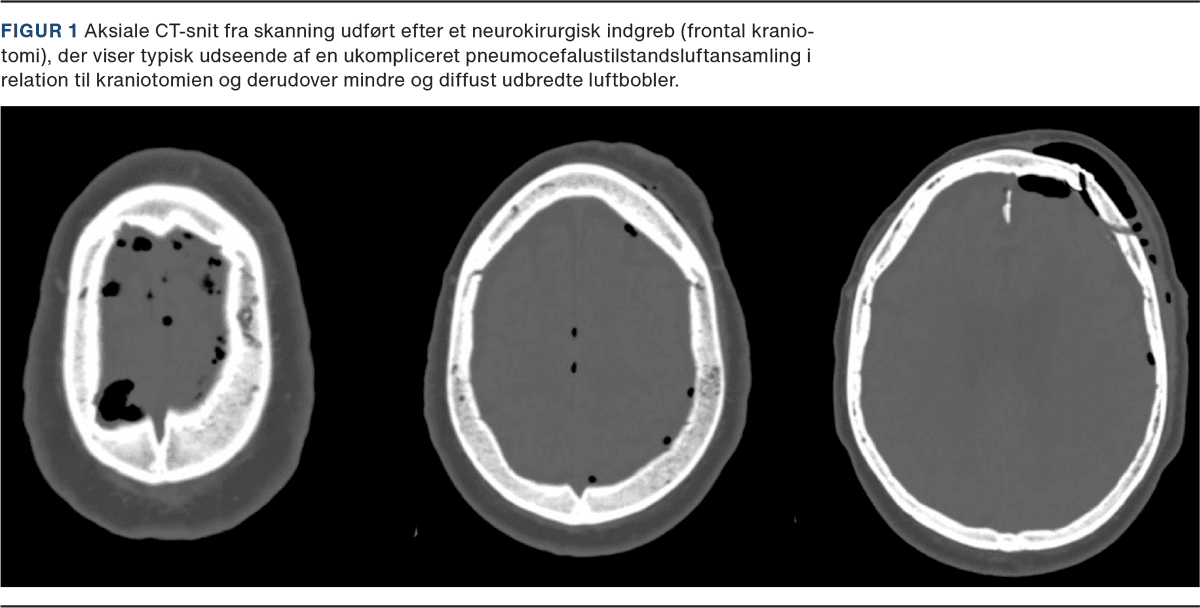

I tillæg til den direkte eksponering for luft ved kirurgiske indgreb, luftembolisering, eller in situ-produktion af bakterier beskrives ofte to hovedmekanismer bag pneumocefalus:

1) »Ball-valve«-mekanismen: Luft kan passere intrakranielt grundet et ekstrakranielt overtryk, f.eks. hoste, nys eller overtryksventilation, men grundet en ventilmekanisme fra intrakranielt væv lukkes åbningen, så luften ikke kan slippe ud igen (Figur 2). Denne mekaniske blev beskrevet af Walter Dandy allerede i 1926 [1].

2) »Inverted soda bottle«-mekanismen: Her antages det, at pneumocefalus opstår som følge af cerebrospinalvæske (CSV)-lækage med følgende negativt intrakranielt tryk (ICP), der fører til, at luft suges ind den modsatte vej [15]. Klinisk ses pneumocefalus ofte samtidig med CSV-lækage, men dette er således ikke obligat [16].